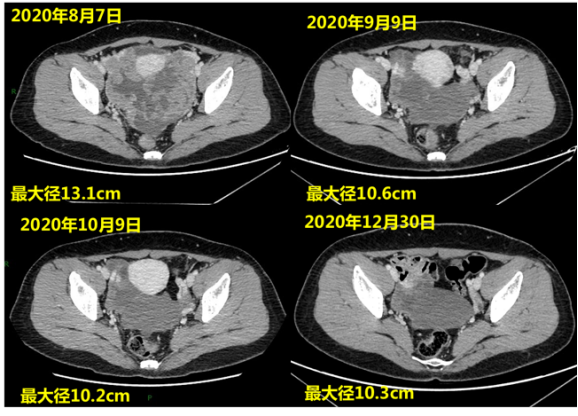

患者董**,男,14岁。2019年年初患者出现恶心呕吐,未重视。2019年4月患者出现头痛,遂行头部MRI示:双侧小脑半球、蚓部、四叠体区占位。患者于2019-4...